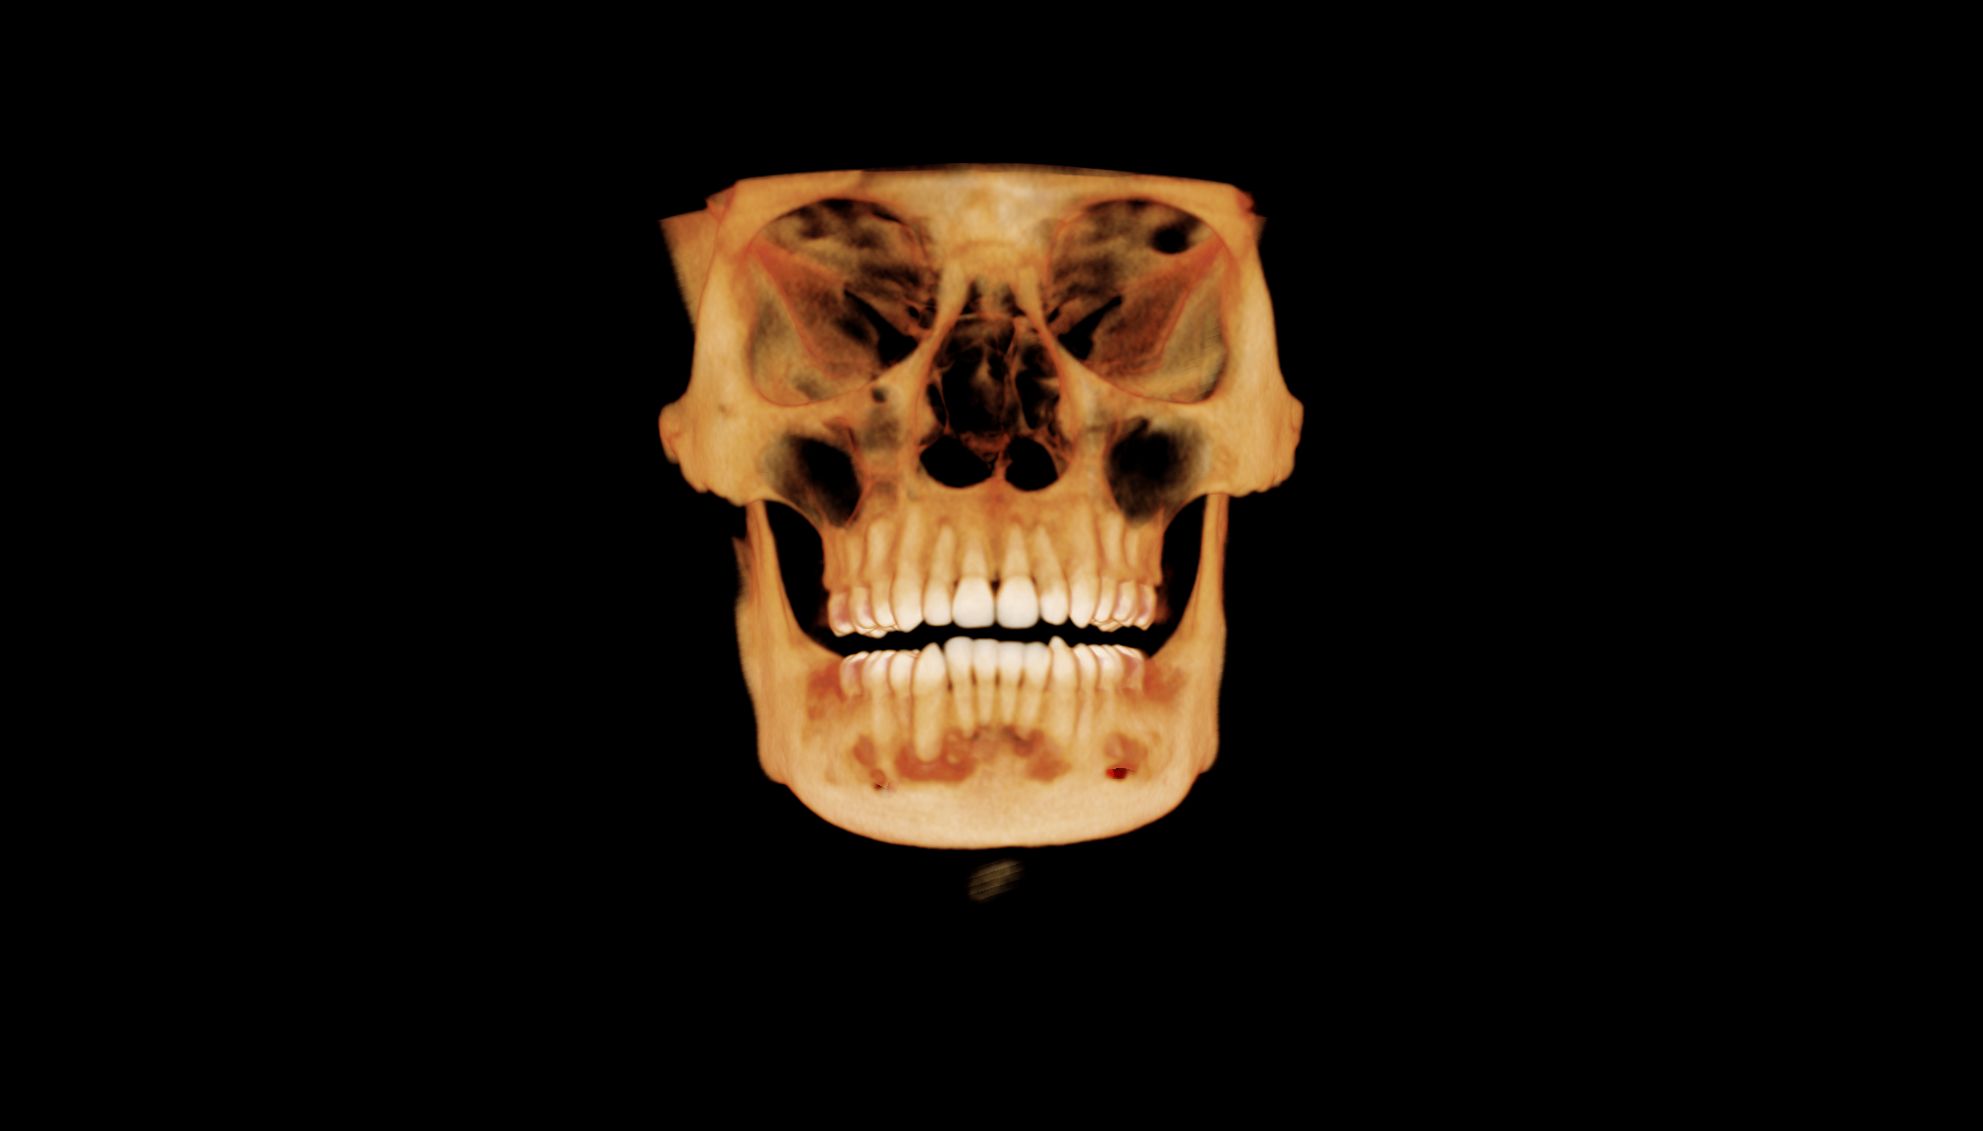

Image Portfolios visually communicate the imaging goals to you and your patient.